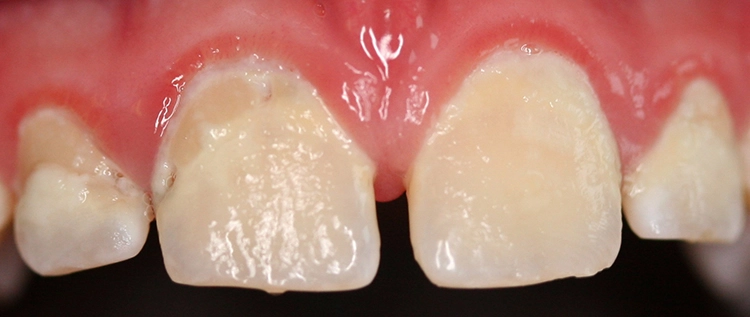

Ein 4-jähriges mäßig kooperatives Kind erscheint zur Kontrolle in der Zahnarztpraxis. Bei der klinischen Untersuchung sind offensichtlich zwei (scheinbar kleinere) approximal kavitierte kariöse Läsionen im Unterkiefer zu sehen sowie Läsionen an den Oberkieferschneidezähnen (Abb. 1a und b). Eine Versorgung dieser Zähne scheint nach klinischer Untersuchung bei diesem Kind noch ambulant möglich.

Dr. J. SchmoeckelAbb. 2: Die Frühkindliche Karies (früher „Nuckelflaschenkaries“ genannt) ist durch ein Auftreten flächiger kariöser Läsionen, die meist zunächst die Oberkieferschneidezähne betreffen, gekennzeichnet. Hauptursachen von ECC sind eine mangelhafte Zahnpflege beim Kleinkind in Kombination mit einem hochfrequenten Konsum zuckerhaltiger Getränke zwischendurch und/oder nachts.

Beim Kleinkind spielt primär die frühkindliche Karies eine Rolle, die initial meist durch kariöse Läsionen an den Oberkieferfrontzähnen gekennzeichnet ist (Abb. 2). Im permanenten Gebiss unterliegen die Kauflächen der durchbrechenden 1. und 2. Molaren insbesondere in der ca. 1,5 Jahre dauernden Durchbruchsphase einem erhöhten Kariesrisiko. Während kieferorthopädischer Maßnahmen mit festsitzenden Apparaturen bei Jugendlichen sollte besonderes Augenmerk auf die Beurteilung der Mundhygiene, wie dem Vorhandensein kariogener Plaque auf Kariesrisikoflächen (Abb. 3), und Kariesaktivität gelegt werden, um frühzeitig präventiv einzugreifen und klinische Bilder mit kariösen Läsionen an fast allen Zähnen möglichst zu vermeiden (Abb. 4).